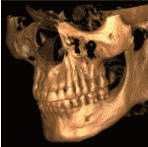

直感的理解による納得のいく診断 |

3D画像(立体画像)により、さらに直感的で分かりやすい説明が可能になりました。

患者様に安心して治療を受けていただけるよう、さらに徹底したインフォームドコンセント(論理的に説明し、納得された治療)を実現します。 |